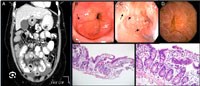

Hình 3. Kết quả CT-scan và mô bệnh học hệ tiêu hóa biểu hiện thâm nhiễm tăng BCAT

oChụp CT-scan:

§Có thể biêu hiện rõ các nốt, các nếp gấp bất thường và dày thành niê mạc dạ dày và ruột non (J Comput Assist Tomogr 1999;23:417) !important;

·Hình ảnh nội soi cũng thấy thay đổi khác nhau và không đặc hiệu. Hình ảnh sung huyết đỏ dễ mụn nát, khuyết lỗ, loét, nếp gấp niêm mạc dạ dày sưng phồng và nhiều thương tổn dạng nốt ở niêm mạc rải rác, đặc biệt ở vùng hang vị. Các phát hiện không đặc hiệu này nhấn mạnh nhu cầu cân phải sinh thiết niêm mạc, trong đó cho thấy thâm nhiễm BCAT trong lớp niêm mạc dạ dày và thâm nhiễm cả bạch cầu lympho, dưỡng bào và bạch cầu đa nhân trung tính. Tiêu chuẩn mô học để chẩn đoán là > !important; 50 BCAT/vi trường độ phóng đại cao trong ít nhất 5 vi trường, không kèm theo các rối loạn khác có tăng BCAT đã biết trước đó. Trong thân vị, thương tổn lan tỏa, trong khi ở hang vị các thương tổn khu trú nhỏ hơn là ưu thế.  Nếu lớp sâu hơn bị liên đới, nội soi sinh thiết có thể không chẩn đoán ra và siêu âm nội soi hay MRI có thể thấy hình ảnh dày thành dạ dày;